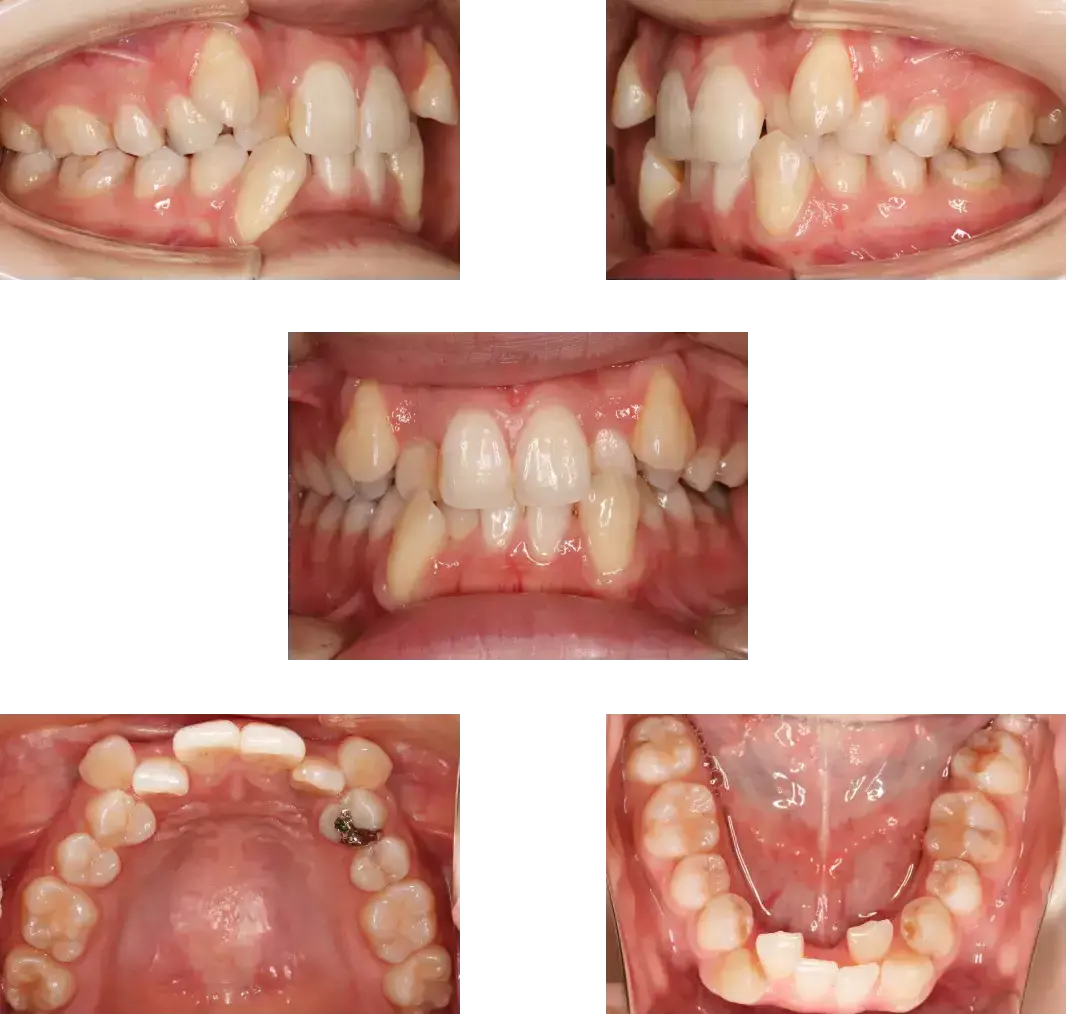

[症例:7] 小児矯正症例

治療前

治療後

[症例:8] 小児矯正症例

| 主訴 | 前歯が1本内側に生えている。 |

| 診断名 | 幅径の不一致、前歯部分反対咬合症例 |

| 治療内容 | 取り外し式の装置で上顎骨の幅径拡大を行い、前歯の被蓋改善を行った。 |

| 年齢 | 8歳 |

| 装置 | 関口先生方式前歯プッシュプレートとシュワルツの拡大装置ミックスの設計 |

| 抜歯部位 | なし |

| 動的治療期間 | 24か月 |

| 治療費(施術料) | 385,000円 |

| リスク・副作用 | 被蓋改善時の前歯歯根吸収、痛み、術後の変化 |

| 主訴 | 上の2番目の前歯が内側に生えてきた |

| 診断名 | 叢生症例、永久歯萌出スペース不足 |

| 治療内容 | 取り外し式の装置で上顎骨の拡大を行い、その後前歯をアクティブプッシュ。 |

| 装置 | シュワルツの拡大装置、上顎2×4装置 |

| 動的治療期間 | 26か月 |

| 治療費(施術料) | 500,000円 (RIVAGE式 子どもinclusive) |

| リスク・副作用 | 痛み、軽度の歯根吸収、術後の変化 |